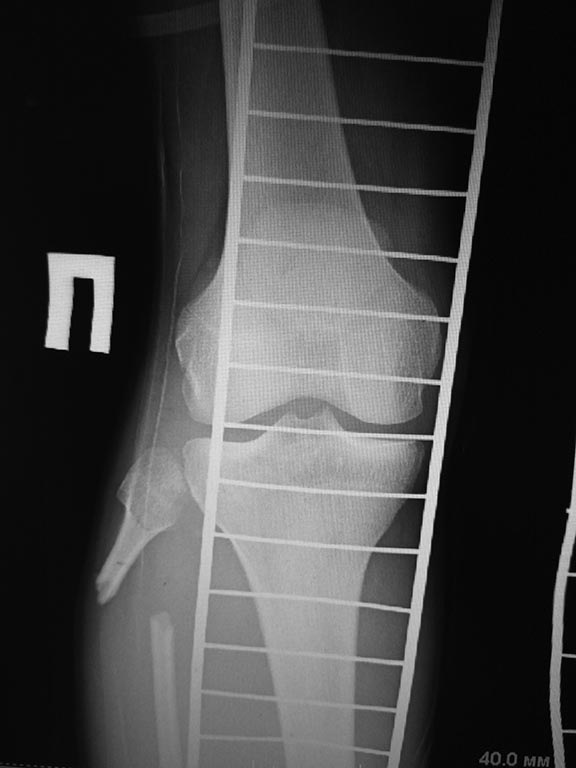

Между первым, вторым и другими возможными вариантами стоит вопрос о жизнеспособности промежуточного фрагмента б/берцовой кости. Ведь не зря микрохирурги сомневаются в его жизнеспособности. Что даст закрытое шинирование + "артродез" (большеберцово-таранный?), если большой фрагмент не жизнеспособен? А остатки эпифиза жизнеспособны? Мы об их состоянии на сегодня ничего не знаем, по снимкам понять ничего нельзя.

Если дистальный эпиметафиз анатомичен и жизнеспособен при адекватных свойствах мягких тканей можно рассмотреть вариант билокального компрессионно-дистанционного э лечения в аппарате с резекцией сомнительного участка бберц кости и проксимальной остеотомией большеберцовой и малоберц кости для дистракции. Хорошо бы КТ голеностопного сустав увидеть.

Спицевой аппарат Илизарова уж больно "хлипенький". Скорее всего, нет должной стабильности. Нет стабильности - нет восстановления кровотока в промежуточных фрагментах. Возникает вопрос о их жизнеспособности (отсутствует периостальная реакция). Нужно начать с аппарата внешней фиксации!!!